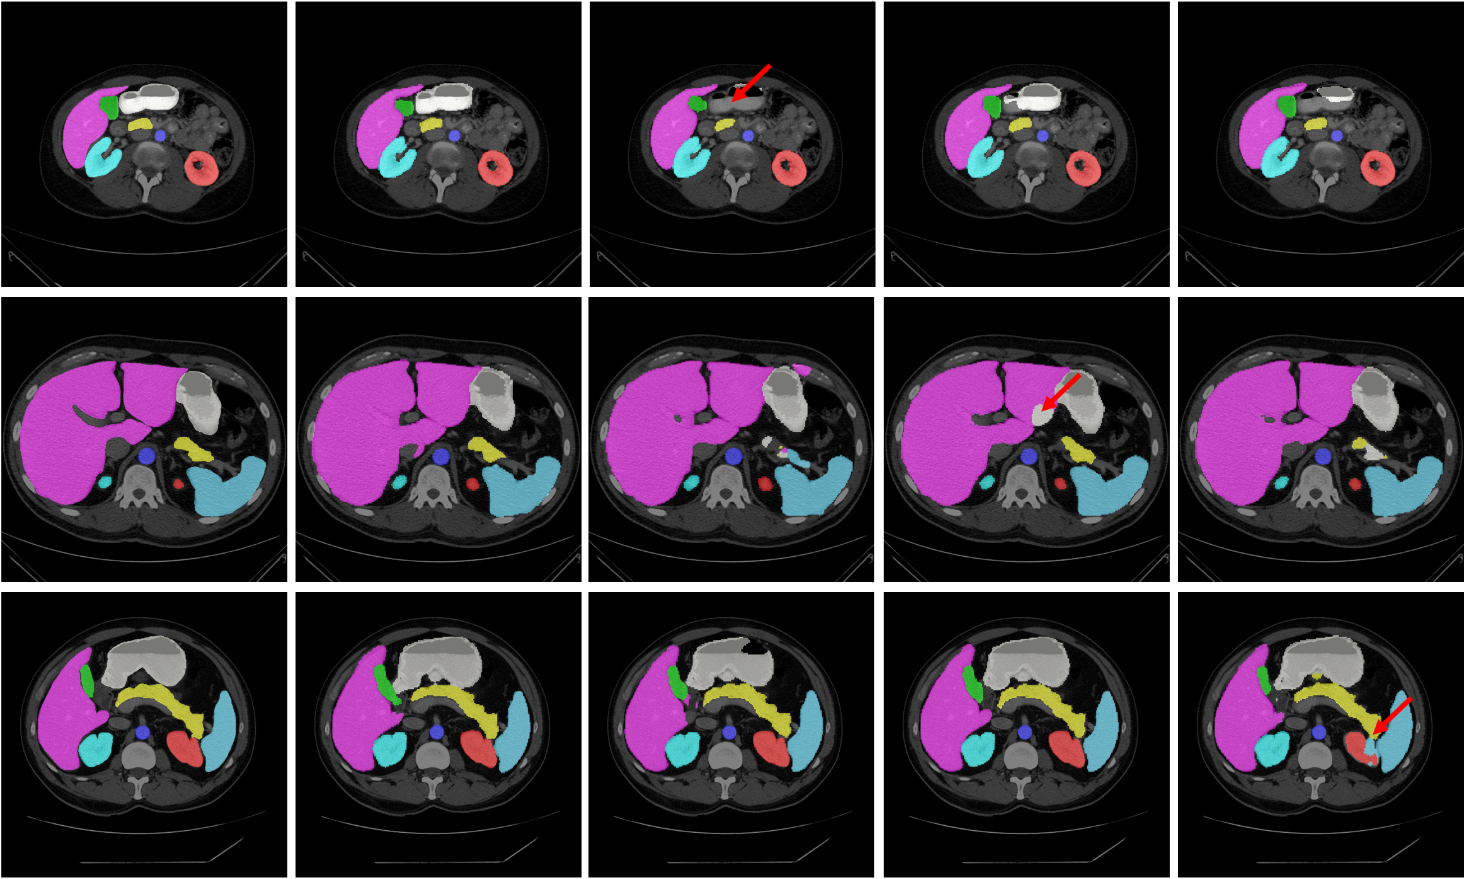

The segmentation results of different methods on the Synapse dataset are shown in the Figure 4. We can see that the other three methods are more likely to under-segment or over segment the organs, for example, the stomach is under-segmented by TransUNet and DeepLabV3+ (as indicated by the red arrow in the third panel of the upper row), and over-segmented by UNet (as indicated by the red arrow in the fourth panel of the second row). Moreover, results in the third row demonstrate that our LeViT-UNet outputs are relatively smoother than those from other methods, which indicates that our method has more advantageous in boundary prediction.